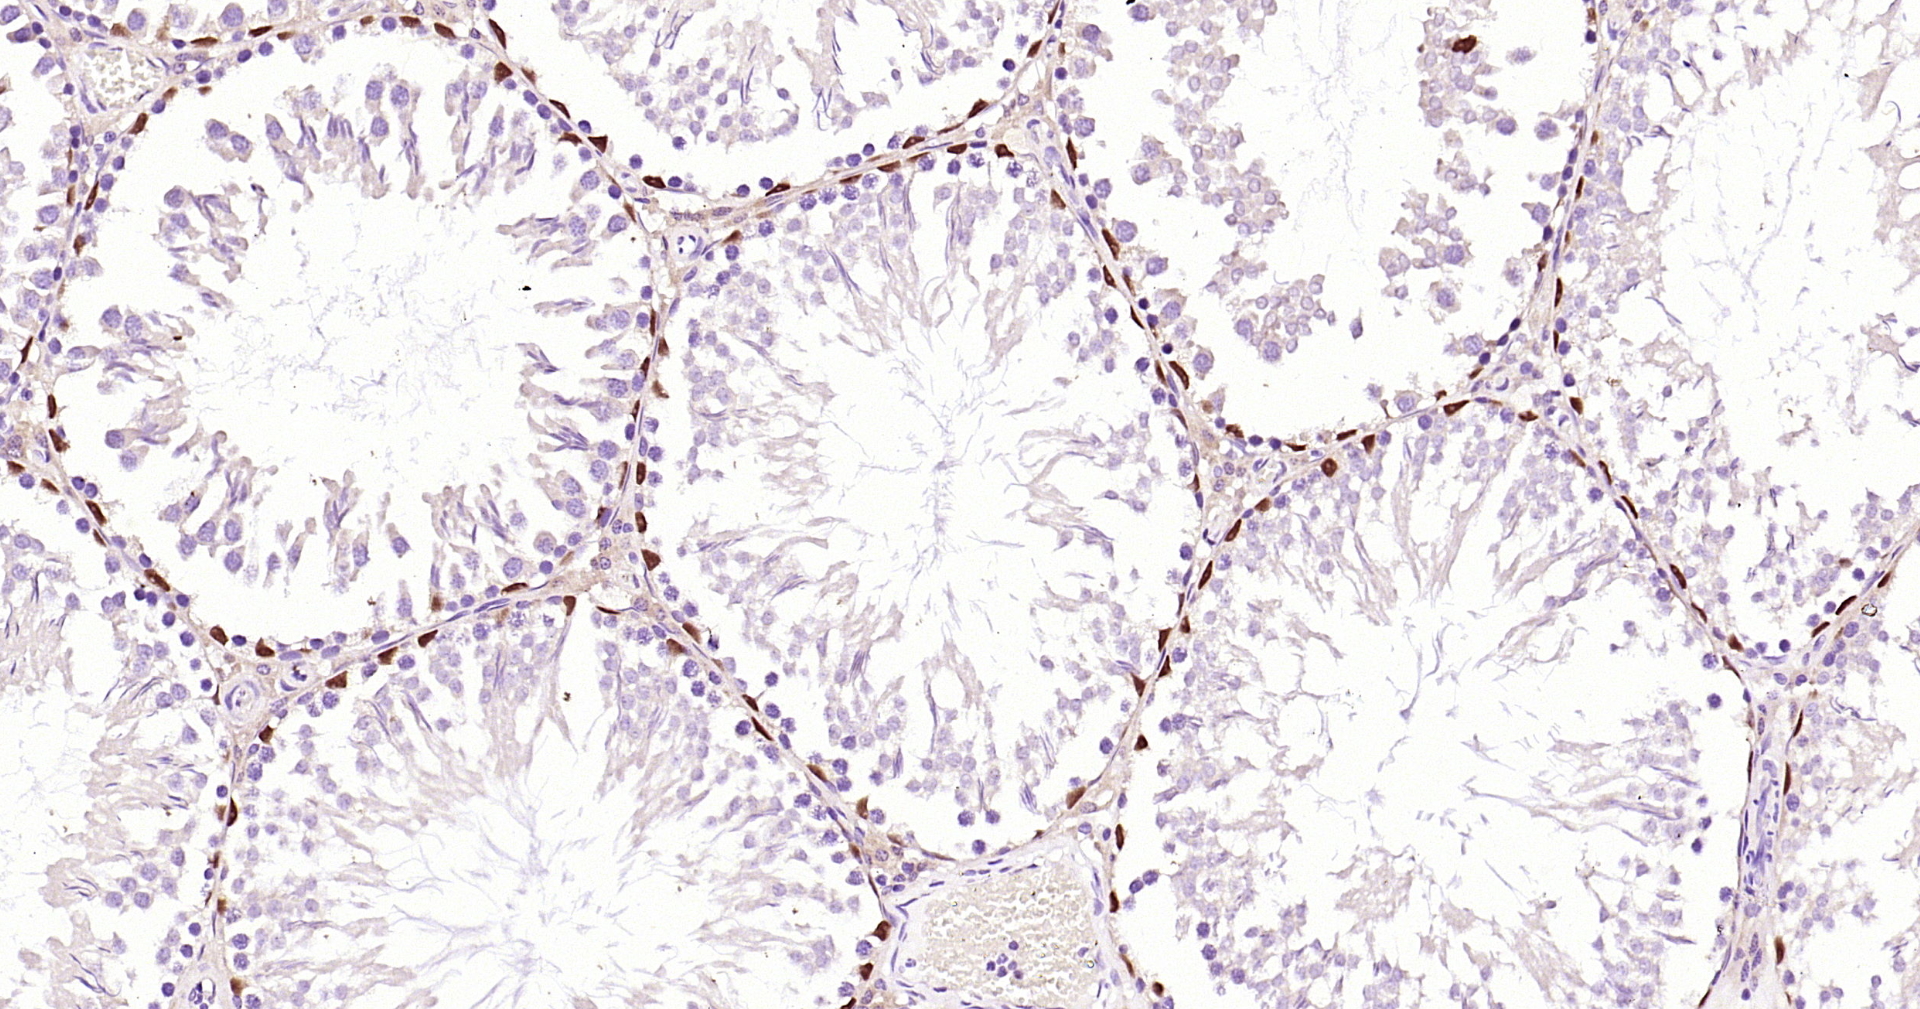

• IHC-P

IHC-P IHC-P1:200-1000